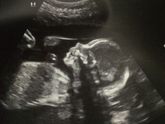

Сходили на УЗИ, малыши растут, в поперечном положении))) но один малыш он изначально был поменьше, но разницами между ними увеличилась ещё на 2 дня. В итоге маленький от большого отстаёт на 9 дней. Как бы это может быть нормой, я знаю. Но с каждым УЗИ … Читать далее

Растут карапузы, радуют маму своими пиночками))) пока радуют! Пока это приятные ощущения, что будет дальше посмотрим)) имена уже придумали, Арсений(Сеня) и Савелий(Сава). Осталось подождать когда родятся и определится, как говорится "ху из ху" ??. А … Читать далее